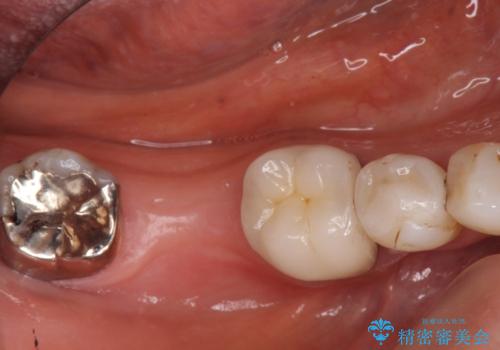

銀歯を白く 虫歯治療

保険適用の銀色のつめもののやり替えを行いました。

- 30.8万円(右上4567 emaxプレスインレー 7万円x4本)費用は治療当時の料金となります

自由診療のインレーの歯型には、シリコンを使用しています。また、処置時には8倍の拡大鏡を用いて、精密に治療しております。